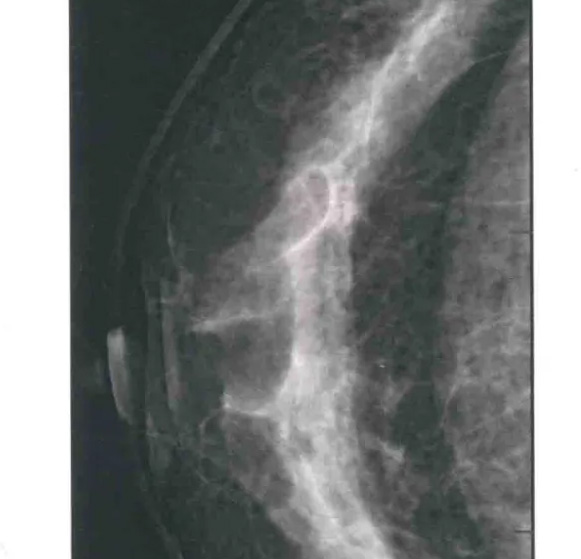

二、圖像顯示要求,含乳腺的基底部及內(nèi)外側(cè)乳腺組織,需要顯示胸肌前緣或胸壁。頭尾位與內(nèi)外斜位乳頭后線長度差≤1厘米;顯示實(shí)質(zhì)后的乳腺組織,乳頭位于切線位,乳腺組織重疊;雙側(cè)乳腺頭尾位照片相對放置,則兩側(cè)乳腺呈球形;影像密度和對比度良好,能顯示0.1毫米細(xì)小鈣化,清晰沒有偽影異物、運(yùn)動偽影和切割偽影等。